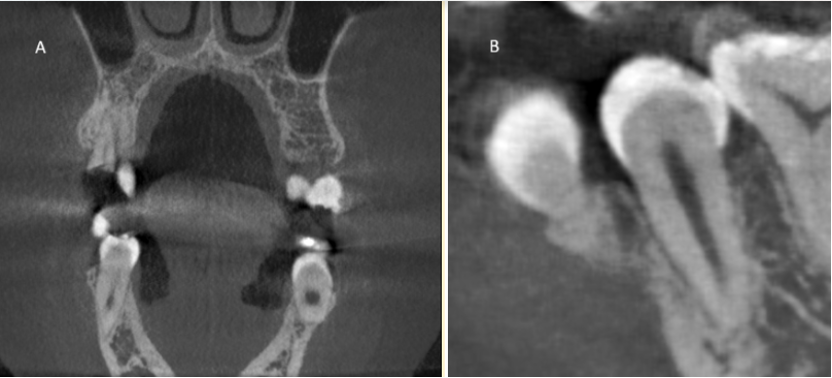

A CBCT A CBCT scan was performed prior to extraction as part of the patient’s standard care. [Figure 1]

Figure 1. A representative coronal slice from the preoperative CBCT scan (A), and a Sagittal close-up (B) view showing tooth #45 in situ (green arrows). This image illustrates the raw data used by the algorithm for 3D reconstruction.